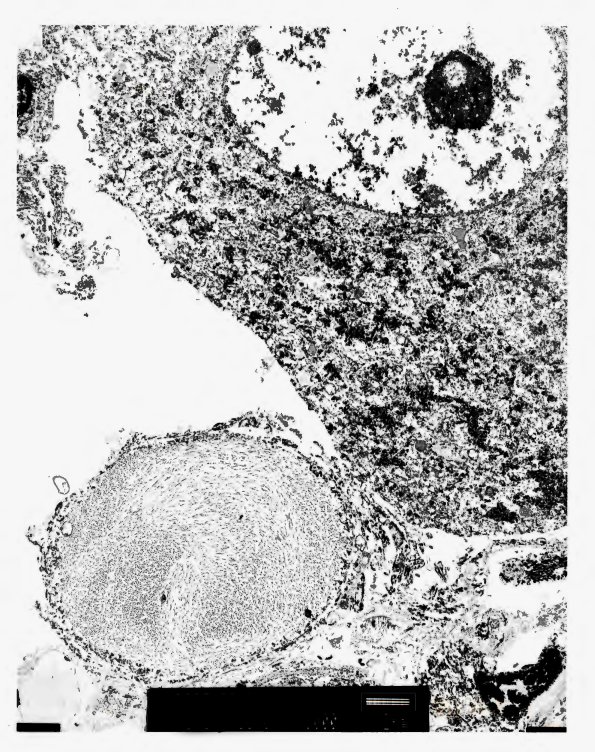

4A6-9 Dystrophic swellings correspond with neurofilament containing argyrophilic spheroids. (electron micrograph)